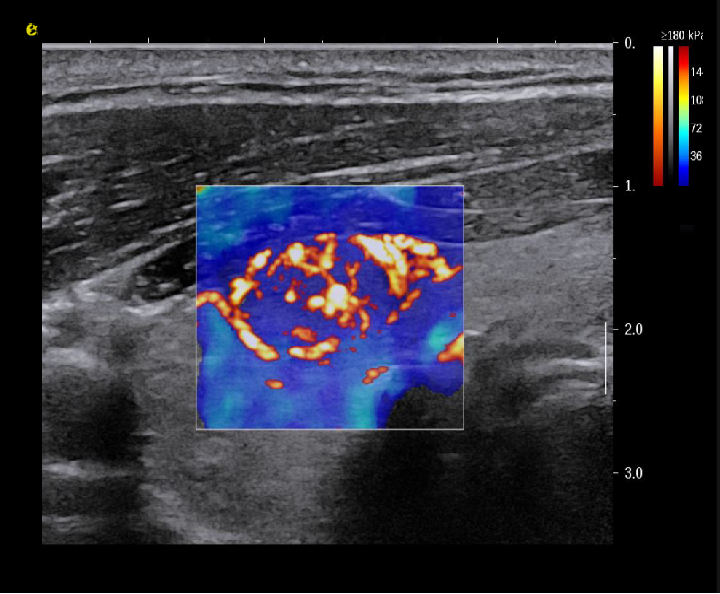

平面波超微细血流显像

能够提供更多真实的组织细小及末梢血管的血流信息,直观的观察组织内部的血管架构及血流形态的情况,提供临床更多有价值的诊断信息。

临床应用:

肿瘤鉴别诊断(肝脏、肾脏、甲状腺、乳腺、  涎腺等)

淋巴结评价(炎症、肿瘤)

肌骨系统临床诊断和疗效监测(关节、滑膜、韧带、肌肉炎症、 损伤等)

斑块内新生血管评估

超声介入术前进针方案提供血流参考信息

超声介入术后疗效评估